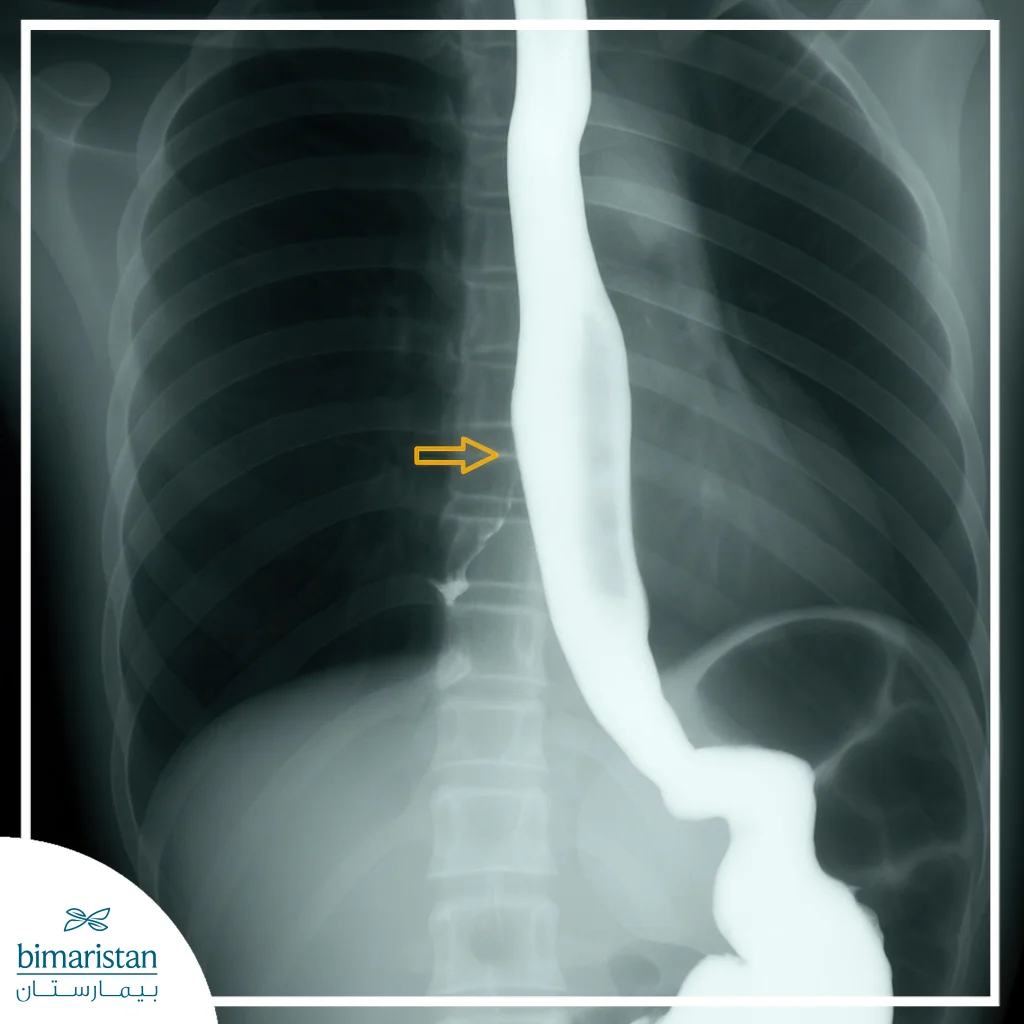

Barium Swallow

This technique is used to visualize the esophagus after swallowing a barium-containing substance, allowing the doctor to see any leakage of the substance into the airways. This method is effective for determining the size and shape of the fistula and helps in planning the appropriate surgical or endoscopic treatment.